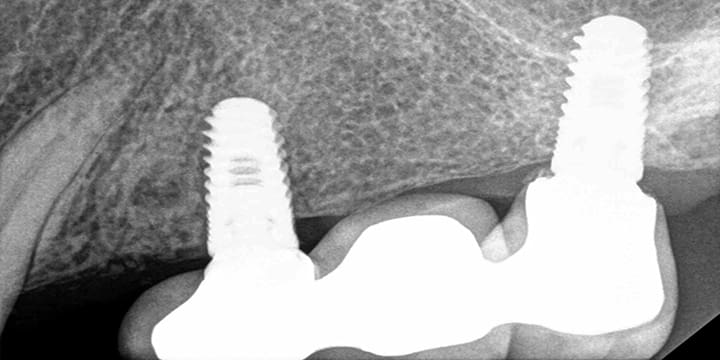

Dental Implant Placement in a Challenging Space

This case highlights Dr. XJamal's expertise in placing a dental implant in a particularly tight area. The "before" image shows the limited narrow apace available. The "after" image shows the seamless placement of the implant, restoring both function and aesthetics.